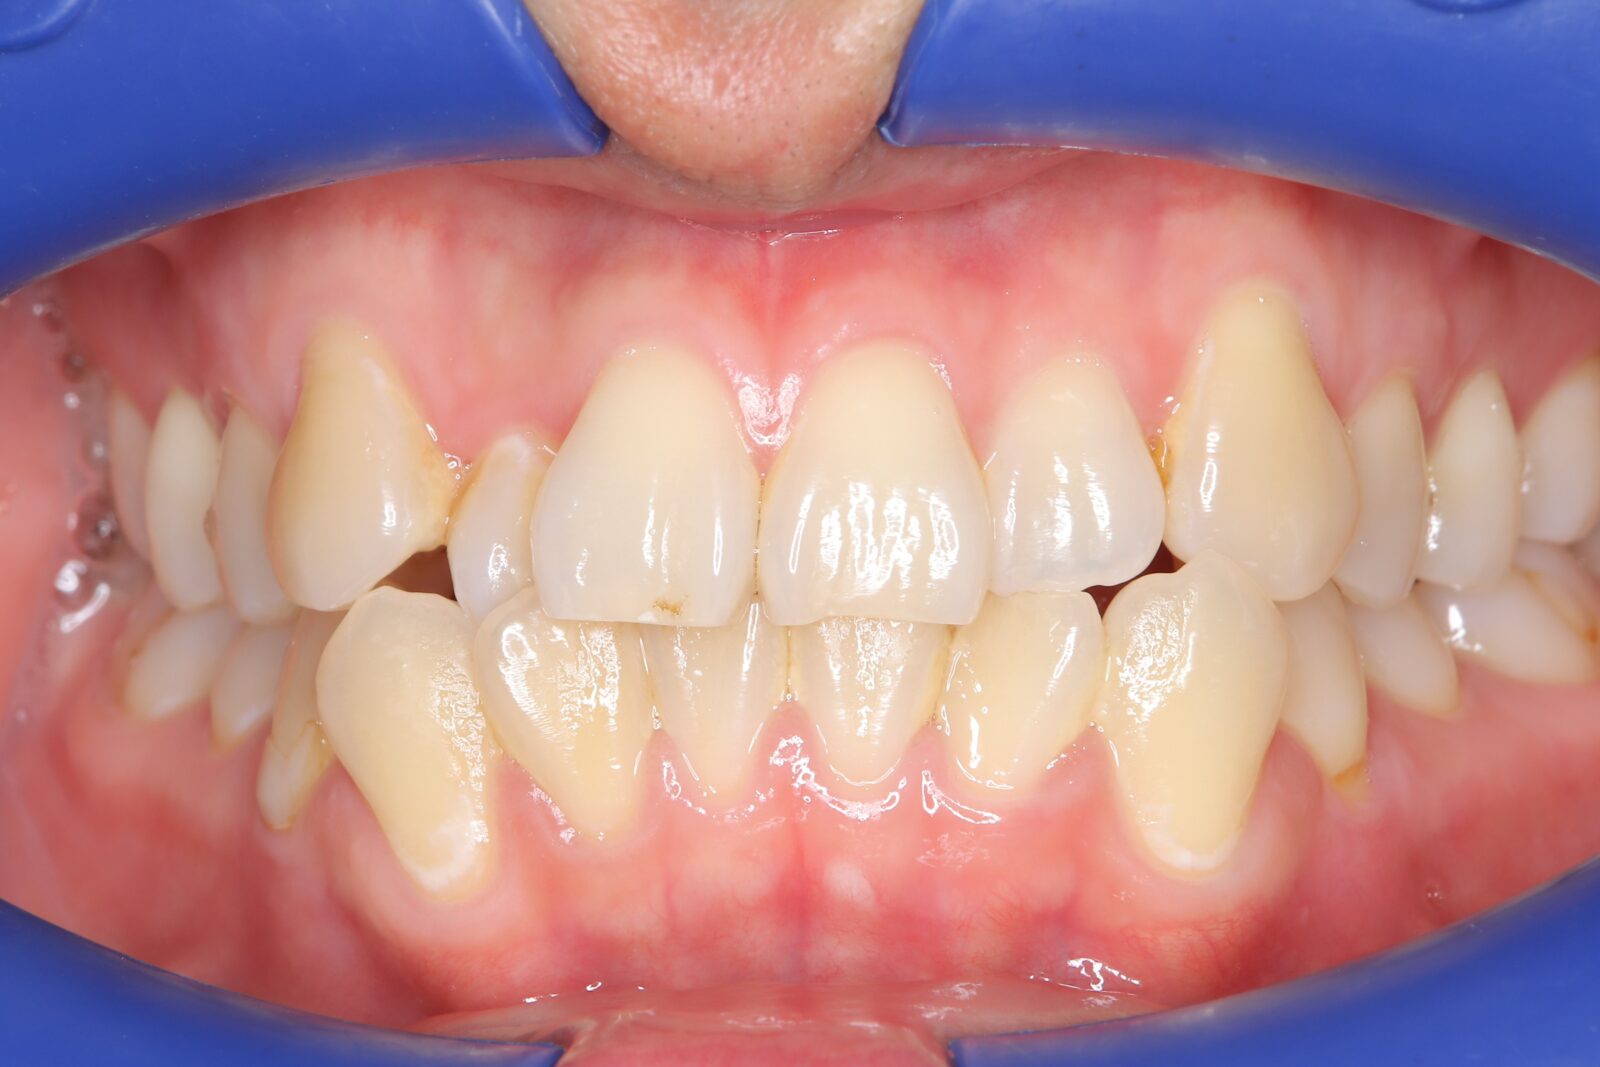

インビザライン(全体矯正)+ホワイトニングコースの症例

上下の前歯の歪みと奥歯のすれ違いをインビザライン(全体矯正)とホワイトニングで綺麗に矯正。

・費用:935,000円(税込)

・治療期間:30ヶ月

・通院回数:30回

・31歳女性

-リスクと副作用-

・長時間マウスピースを装着するため、むし歯や歯周病のリスクがある。治療後はリテーナーを装着しないと後戻りしてしまうリスクがある。

・ホワイトニング剤の影響で知覚過敏が起こる可能性がある。色が徐々に戻る可能性がる。